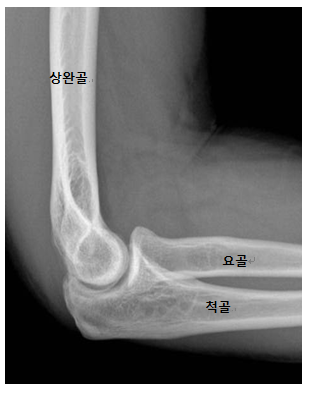

팔꿈치 관절은 상완골(팔뚝의 위쪽 뼈), 요골(팔뚝의 아래쪽에서 엄지 쪽 뼈), 그리고 척골(팔뚝의 아래쪽에서 소지 쪽 뼈)의 만남으로 구성됩니다. 이 관절은 팔의 굴곡과 신전, 그리고 전완의 회전을 가능하게 하는 중요한 역할을 합니다.

상완골: 팔뚝의 위쪽 부분을 이루며, 팔꿈치 관절에서 중요한 역할을 합니다.

요골: 팔뚝 아래쪽의 한쪽 뼈로, 엄지 손가락 쪽에 위치합니다.

척골: 팔뚝 아래쪽의 다른 한쪽 뼈로, 소지 쪽에 위치합니다.